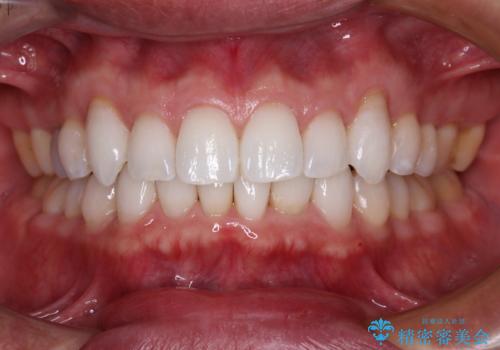

前歯のがたつきをなおしたい マウスピース矯正

担当医 大元洋佑

![[ マウスピース矯正 ] 前歯の角度・がたつきを治したい。の症例 治療前](https://seimitsushinbi.jp/wp/wp-content/uploads/2024/02/IMG_7820-500x350.jpg?v=1707810350)

![[ マウスピース矯正 ] 前歯の角度・がたつきを治したい。の症例 治療後](https://seimitsushinbi.jp/wp/wp-content/uploads/2024/02/8334681fa61954fc45ff8cef14f33166-500x350.jpg?v=1707810480)